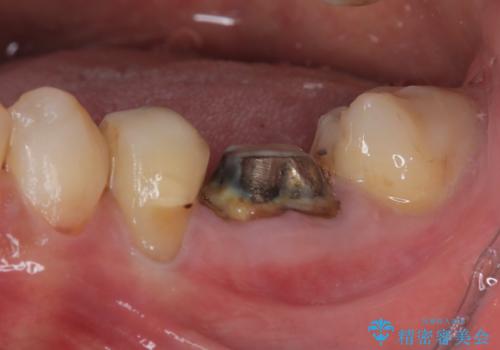

当院では、他院で抜歯と言われてきた歯を何とか保存する治療を多く行ってきましたが、レントゲン上で確認できるほど割れてしまっている歯はさすがに要抜歯と説明をし、インプラント治療を行うこととしました。

下顎大臼歯の抜歯即時埋入インプラント治療では、複数ある歯根のうち、後方の歯根部にインプラントを埋入することで一般的であり、今回破折して骨吸収が著しいのは前方の歯根であったため、事前に仮歯を用意した上で、抜歯即時埋入インプラントによる補綴治療を行うこととしました。

来院されるまではインプラント治療を躊躇されていましたが、抜歯即時埋入により、単回の外科処置で治療が終えられることのメリットを理解され、インプラントによる補綴治療を行いました。